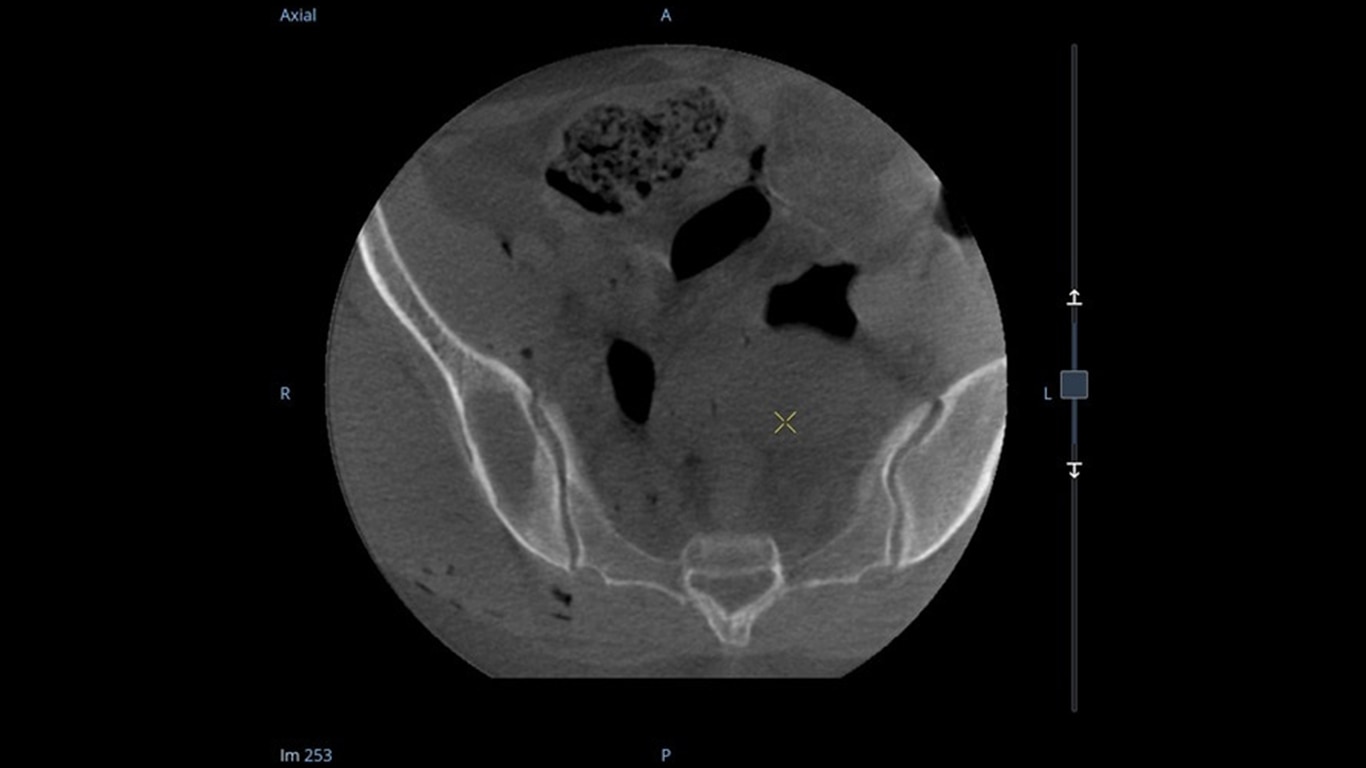

Analysieren Sie Ihre Scans mit dem GE Volume Viewer – genauso intuitiv wie am CT. Profitieren Sie von der vollständigen Darstellung axialer, koronarer und sagittaler Ebenen sowie von MIP-Ansichten und 3D-Visualisierungen im VR-Modus. Scrollen Sie durch bis zu 512 Schichten mit nahtloser Anpassung der Schichtdicke – für eine präzise Befundung direkt im OP.